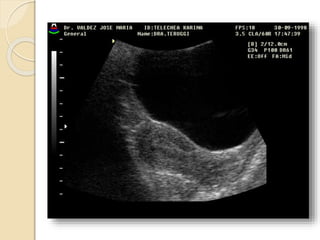

Quistes Endometrósicos:

Clínicamente se manifiesta por dismenorrea,

dispareunia e infertilidad.

La lesion mas detectable por la imágenes esta

constituida por los quistes endometrosicós

(endometriomas) que se forman a partir de los

implantes ováricos configurando los quistes

“achocolatados”.

Se observan quistes de paredes relativamente

gruesas e irregulares con débiles ecos en su

interior debido al contenido hemático.